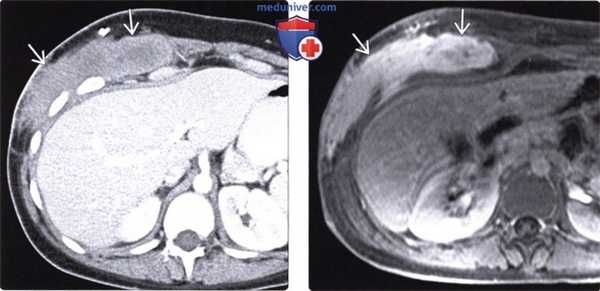

(Слева) На аксиальной КТ с контрастным усилением визуализируется слабо накапливающее контраст объемное образование инфильтративного характера, расположенное в мышцах передней брюшной стенки с правой стороны на месте инцизионного рубца после операции.

(Справа) На аксиальной Т1 МР томограмме с контрастным усилением и жироподавлением у этого же пациента определяется относительно интенсивное накопление контраста опухолью, которая, (также, как и при КТ) скорее всего, имеет инфильтративный характер роста и нечеткие контуры. В подобных случаях отличить десмоидную опухоль от любого другого злокачественного новообразования мягких тканей можно только с помощью гистологического исследования.